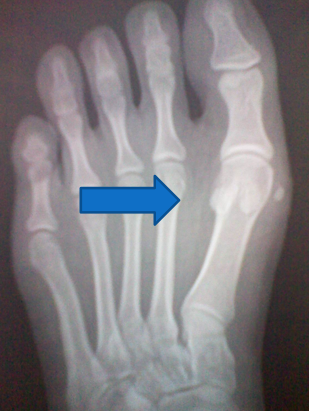

1:前后位观察和测量拇外翻角(HAA)  :拇趾跖骨中轴线与近节趾骨中轴线之夹角。正常为15°~20°

第1、2跖骨间夹角(IMA):  第1、2跖骨中轴线之夹角。正常为9 °拇外翻时此角通常大于正常。

拇外翻的分度与分类足踝外科学中Mann将拇外翻分为轻、中、重三度1.轻度  第1跖骨头内侧突出并有疼痛。HAA<30°,一部分畸形可由于趾骨间关节外翻引起,跖趾关节一般是适合的,IMA通常<13°,胫侧籽骨一般位于正常位置或有轻度移位,位于位置4。2.中度  拇趾外偏挤压第2趾,拇趾一般有旋前畸形,HAA30°~40°,IMA通常13°~ 16°,胫侧籽骨有明显脱位,位于位置6~7。3.重度  拇指外偏挤压第2趾形成骑跨趾,拇趾有中重度的旋前畸形,HAA>40°,IMA通常>16°,第2趾跖骨头下形成转移性跖骨痛。胫侧籽骨脱位于跖骨头腓侧缘外。